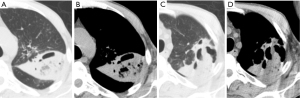

Cavitation within areas of consolidation is a sign of necrotizing pneumonia, often caused by pathogens such as Staphylococcus aureus and Klebsiella pneumoniae. These bacteria are more likely to induce cavitation (Figure 4) (7,8,13). Occasionally, Staphylococcus aureus can occasionally lead to the formation of pneumatoceles, particularly in children (14). Pneumatoceles are thin-walled, cysts that may contain air-fluid levels and typically resolve spontaneously within weeks to a few months (14).

In contrast to cavitating pneumonia, which presents with residual consolidation around the cavity, a lung abscess is a more established process, typically showing little to no surrounding consolidation (7). Imaging findings for lung abscesses typically include cavitary lung lesions with or without fluid levels, variable wall thickness (5–15 mm), peripheral contrast enhancement, and a necrotizing center (Figure 5) (7). If the abscess is located peripherally, focal pleural thickening or an empyema may be present (7).